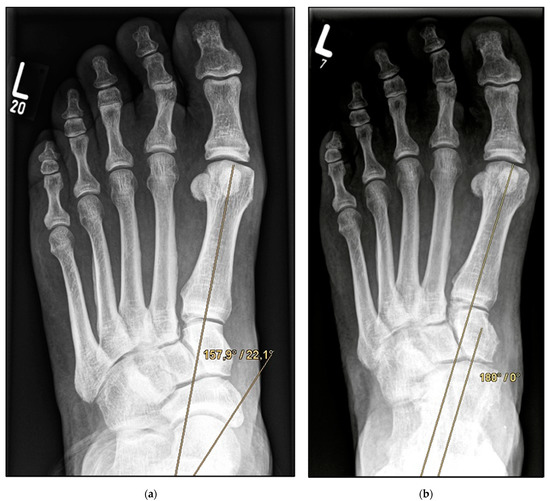

Figure 4.

Pre- and post-operative radiographic findings of double arthrodesis, left foot. (a) Anteroposterior view pre-operative, (b) anteroposterior view post-operative.

Double Arthrodesis (Group B). Firstly, subtalar arthrodesis was performed via a lateral subtalar approach. Care was taken to ensure thorough resection of the articular surfaces and extensive release to achieve adequate correction of the valgus deformity and avoid the development of pseudarthrosis. Here, too, the insertion of autologous cancellous bone was considered obligatory. Fixation was achieved by means of two percutaneously inserted lag screws (diameter of 6.5 mm). The subsequent talonavicular arthrodesis was performed as previously described (Figure 4a,b and Figure 5a,b).